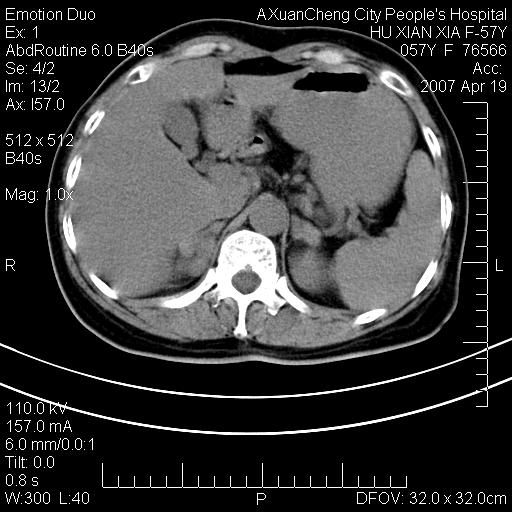

标题: CT7778:[原创]F,57Y腹痛待查,胸片提示肺部占位,应当很典型 [打印本页]

标题: CT7778:[原创]F,57Y腹痛待查,胸片提示肺部占位,应当很典型

胸片提示肺部占位

1.双侧肾上腺占位,转移首先考虑。

2.肝硬化,门静脉高压;肝左叶内侧段病灶建议增强。

双侧肾上腺结节样肿块,结合肺部肿块,考虑肺癌肾上腺转移。

双侧肾上腺及腹膜后淋巴结增大,结合胸片提示肺部占位,考虑肺癌双侧肾上腺及腹膜后淋巴结转移.